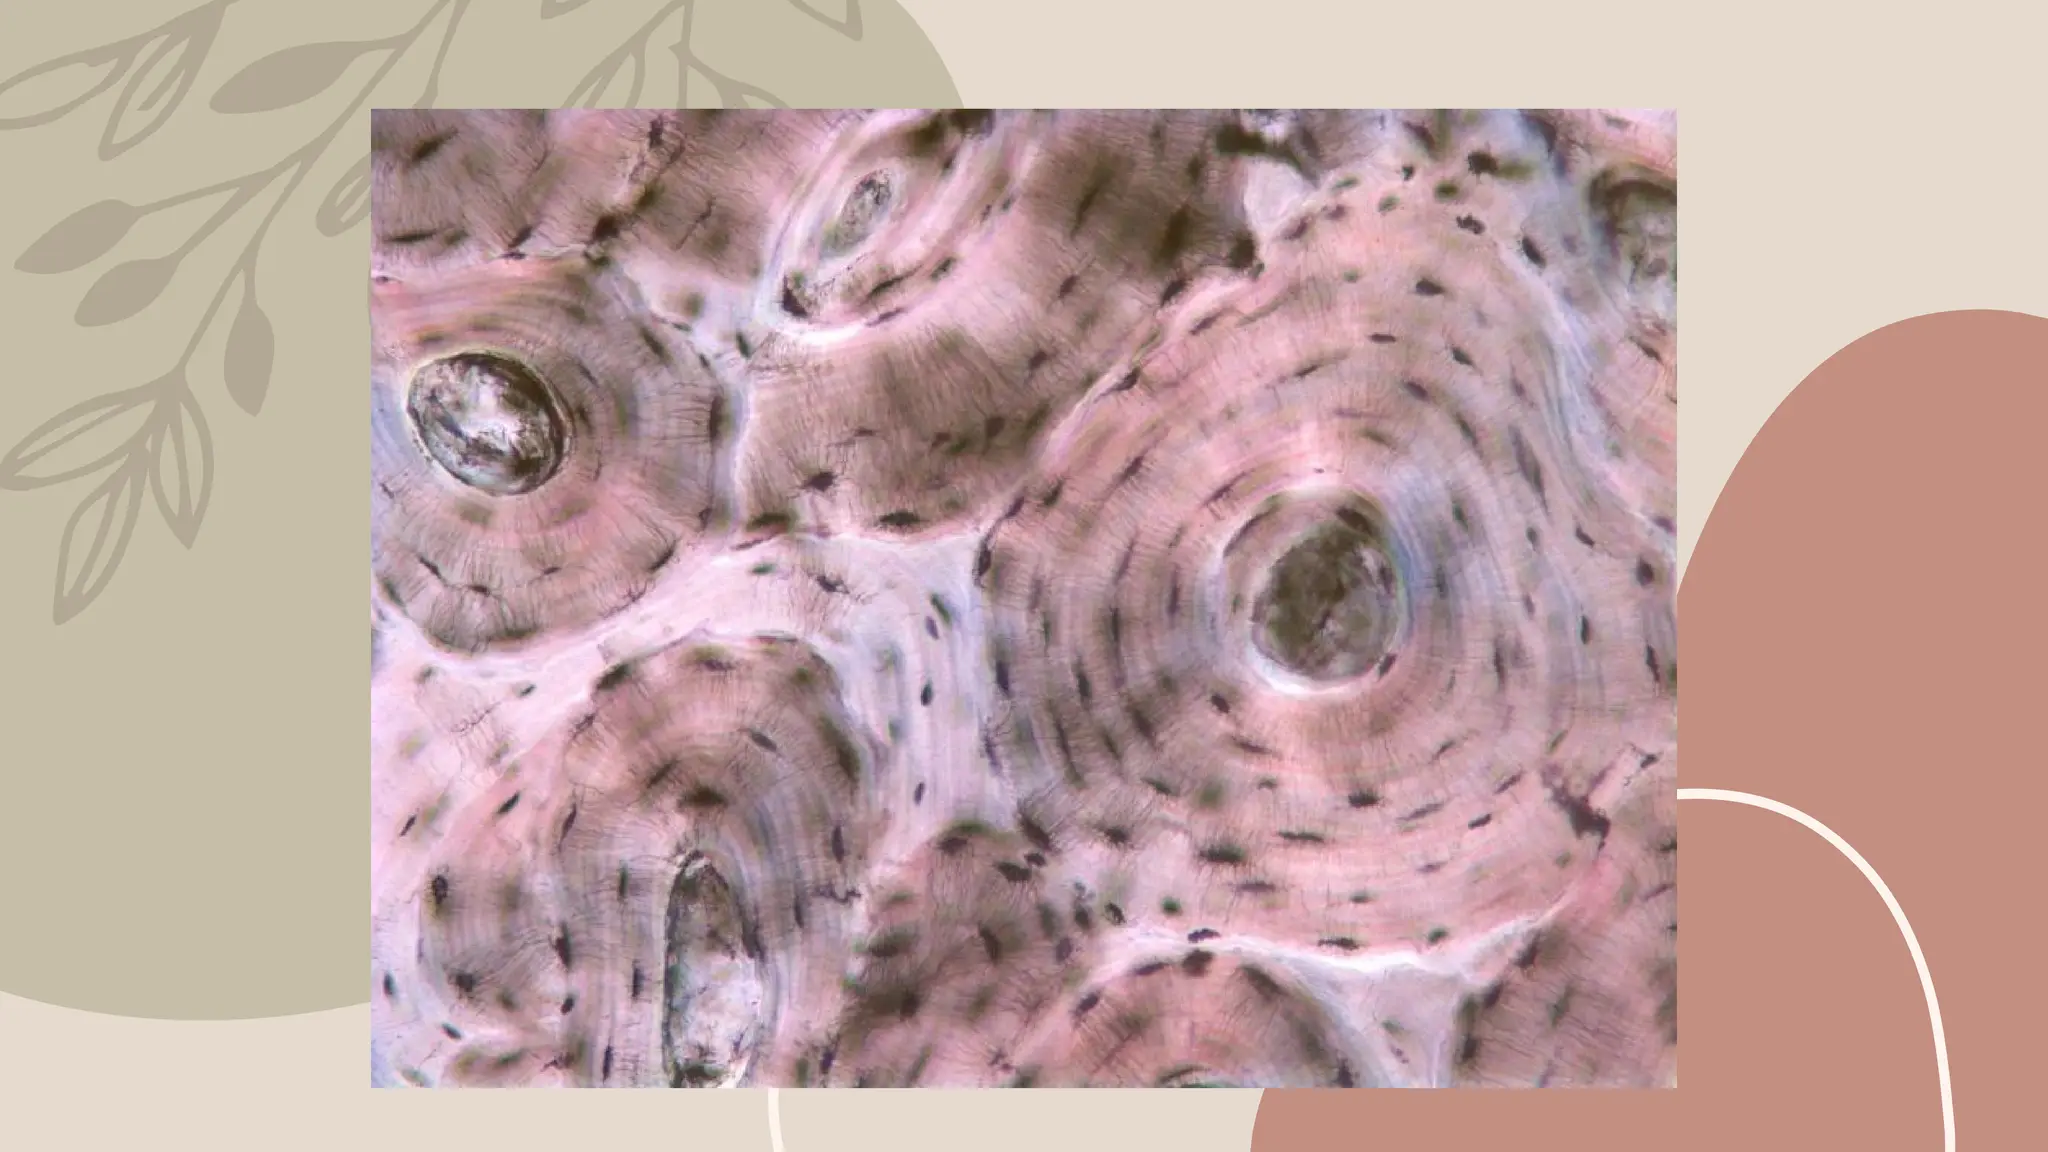

Classification of connective tissue

• Loose (holds organs in place)

• Dense (Tendons and ligaments)

PROPER:

• Cartilage (structure and cushioning)

• Bone (Support and protection)

SUPPORTING:

• Blood (transport)

• Lymph (Immunity)

FLUID:

Connective Tissue ●Functions: ○Support ○Packages andcushions organs ○Transports materials. ●Structure: ○Matrix = ground substance with fibers (elastin, collagen, reticular) and cells.

Classification of connectivetissue • Loose (holds organs in place) • Dense (Tendons and ligaments) PROPER: • Cartilage (structure and cushioning) • Bone (Support and protection) SUPPORTING: • Blood (transport) • Lymph (Immunity) FLUID:

• #20 Loose connective tissue - see table

• #21 Dense connective tissue - see table

• #22 Cartilage

• #23 Cartilage

• #24 Cartilage